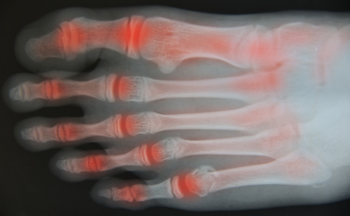

The Impact of Psoriatic Arthritis on the Feet and Ankles

Psoriatic arthritis, or PsA, is a type of inflammatory arthritis that can manifest in individuals with the autoimmune skin condition psoriasis. This form of arthritis primarily affects the feet and ankles, bringing about inflammation and pain in the joints and supporting structures. PsA is frequently associated with various other foot conditions, including Achilles tendonitis, dactylitis, and plantar fasciitis. Achilles tendonitis is characterized by a painful inflammation of the tendon connecting the calf muscles to the heel where it attaches to the heel bone. Dactylitis involves severe inflammation around the toe joints, leading to swelling that gives the toes a sausage-like appearance and induces rigidity and pain when flexing. Plantar fasciitis refers to inflammation where the plantar fascia attaches to the heel bone, causing discomfort and hindrance in movement. As PsA progresses, it can significantly impede walking and performing daily activities, imposing substantial discomfort and limiting one's ability to engage in regular life pursuits. A cure for PsA does not exist yet, but various treatment options are available to manage the condition, slow its progression, and alleviate the associated symptoms. If you suspect or experience symptoms indicative of psoriatic arthritis, it is strongly suggested that you seek help from a qualified podiatrist for a proper diagnosis and personalized treatment.

Arthritic Foot Care

Arthritis is a term that is commonly used to describe joint pain. The condition itself can occur to anyone of any age, race, or gender, and there are over 100 types of it. Nevertheless, arthritis is more commonly found in women compared to men, and it is also more prevalent in those who are overweight. The causes of arthritis vary depending on which type of arthritis you have. Osteoarthritis for example, is often caused by injury, while rheumatoid arthritis is caused by a misdirected immune system.

- Swelling

- Pain

- Stiffness

- Decreased Range of Motion

Arthritic symptoms range in severity, and they may come and go. Some symptoms stay the same for several years but could potentially get worse with time. Severe cases of arthritis can prevent its sufferers from performing daily activities and make walking difficult.

Risk Factors

- Occupation – Occupations requiring repetitive knee movements have been linked to osteoarthritis

- Obesity – Excess weight can contribute to osteoarthritis development

- Infection – Microbial agents can infect the joints and trigger arthritis

- Joint Injuries – Damage to joints may lead to osteoarthritis

- Age – Risk increases with age

- Gender –Most types are more common in women

- Genetics – Arthritis can be hereditary

If you suspect your arthritis is affecting your feet, it is crucial that you see a podiatrist immediately. Your doctor will be able to address your specific case and help you decide which treatment method is best for you.